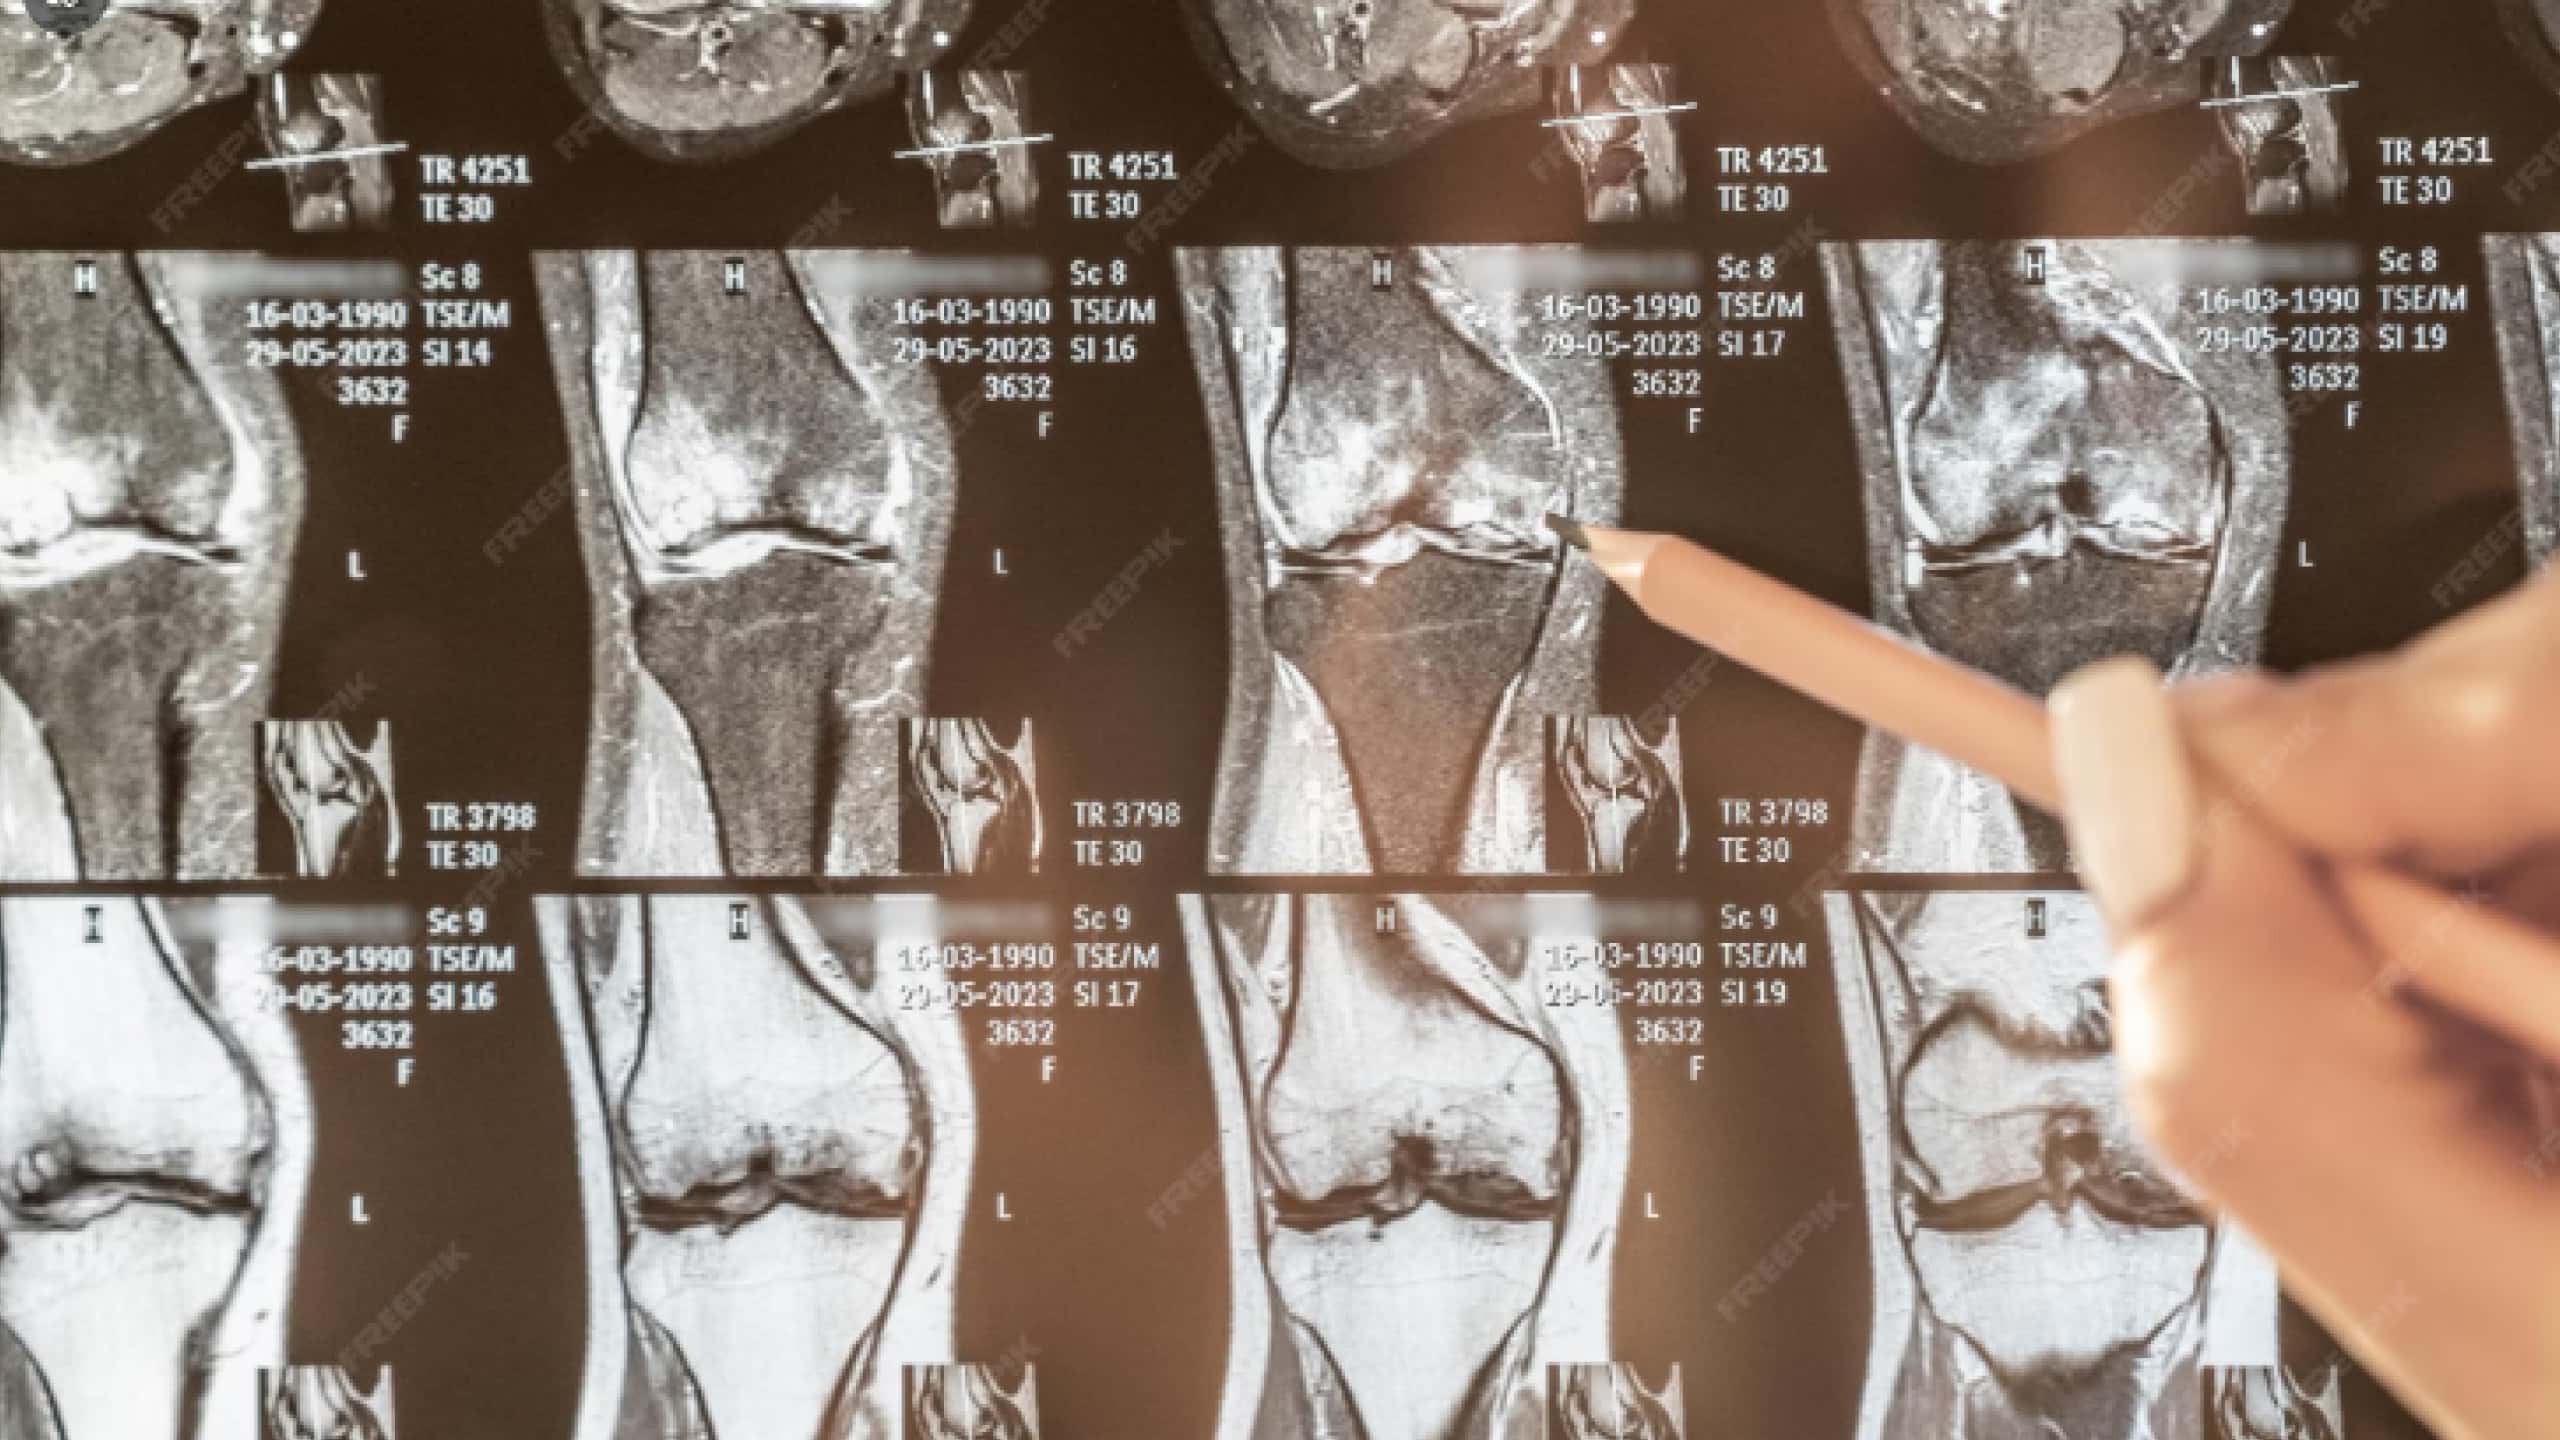

무릎관절증은 관절 연골이 점진적으로 닳으면서 염증과 통증이 발생하는 퇴행성 질환이다. 흔히 무릎관절염과 혼용되지만, 퇴행성 변화 중심의 개념이다. 초기에는 활동 시 통증이 나타나며, 진행되면 안정 시 통증이 지속될 수 있다.

주요 증상으로는 통증과 부기, 관절의 뻣뻣함, 계단 오르내림 시 통증 악화, 관절 운동 범위 감소 등이 있다. 이러한 증상 완화를 위해 다양한 관절주사 치료가 활용된다.